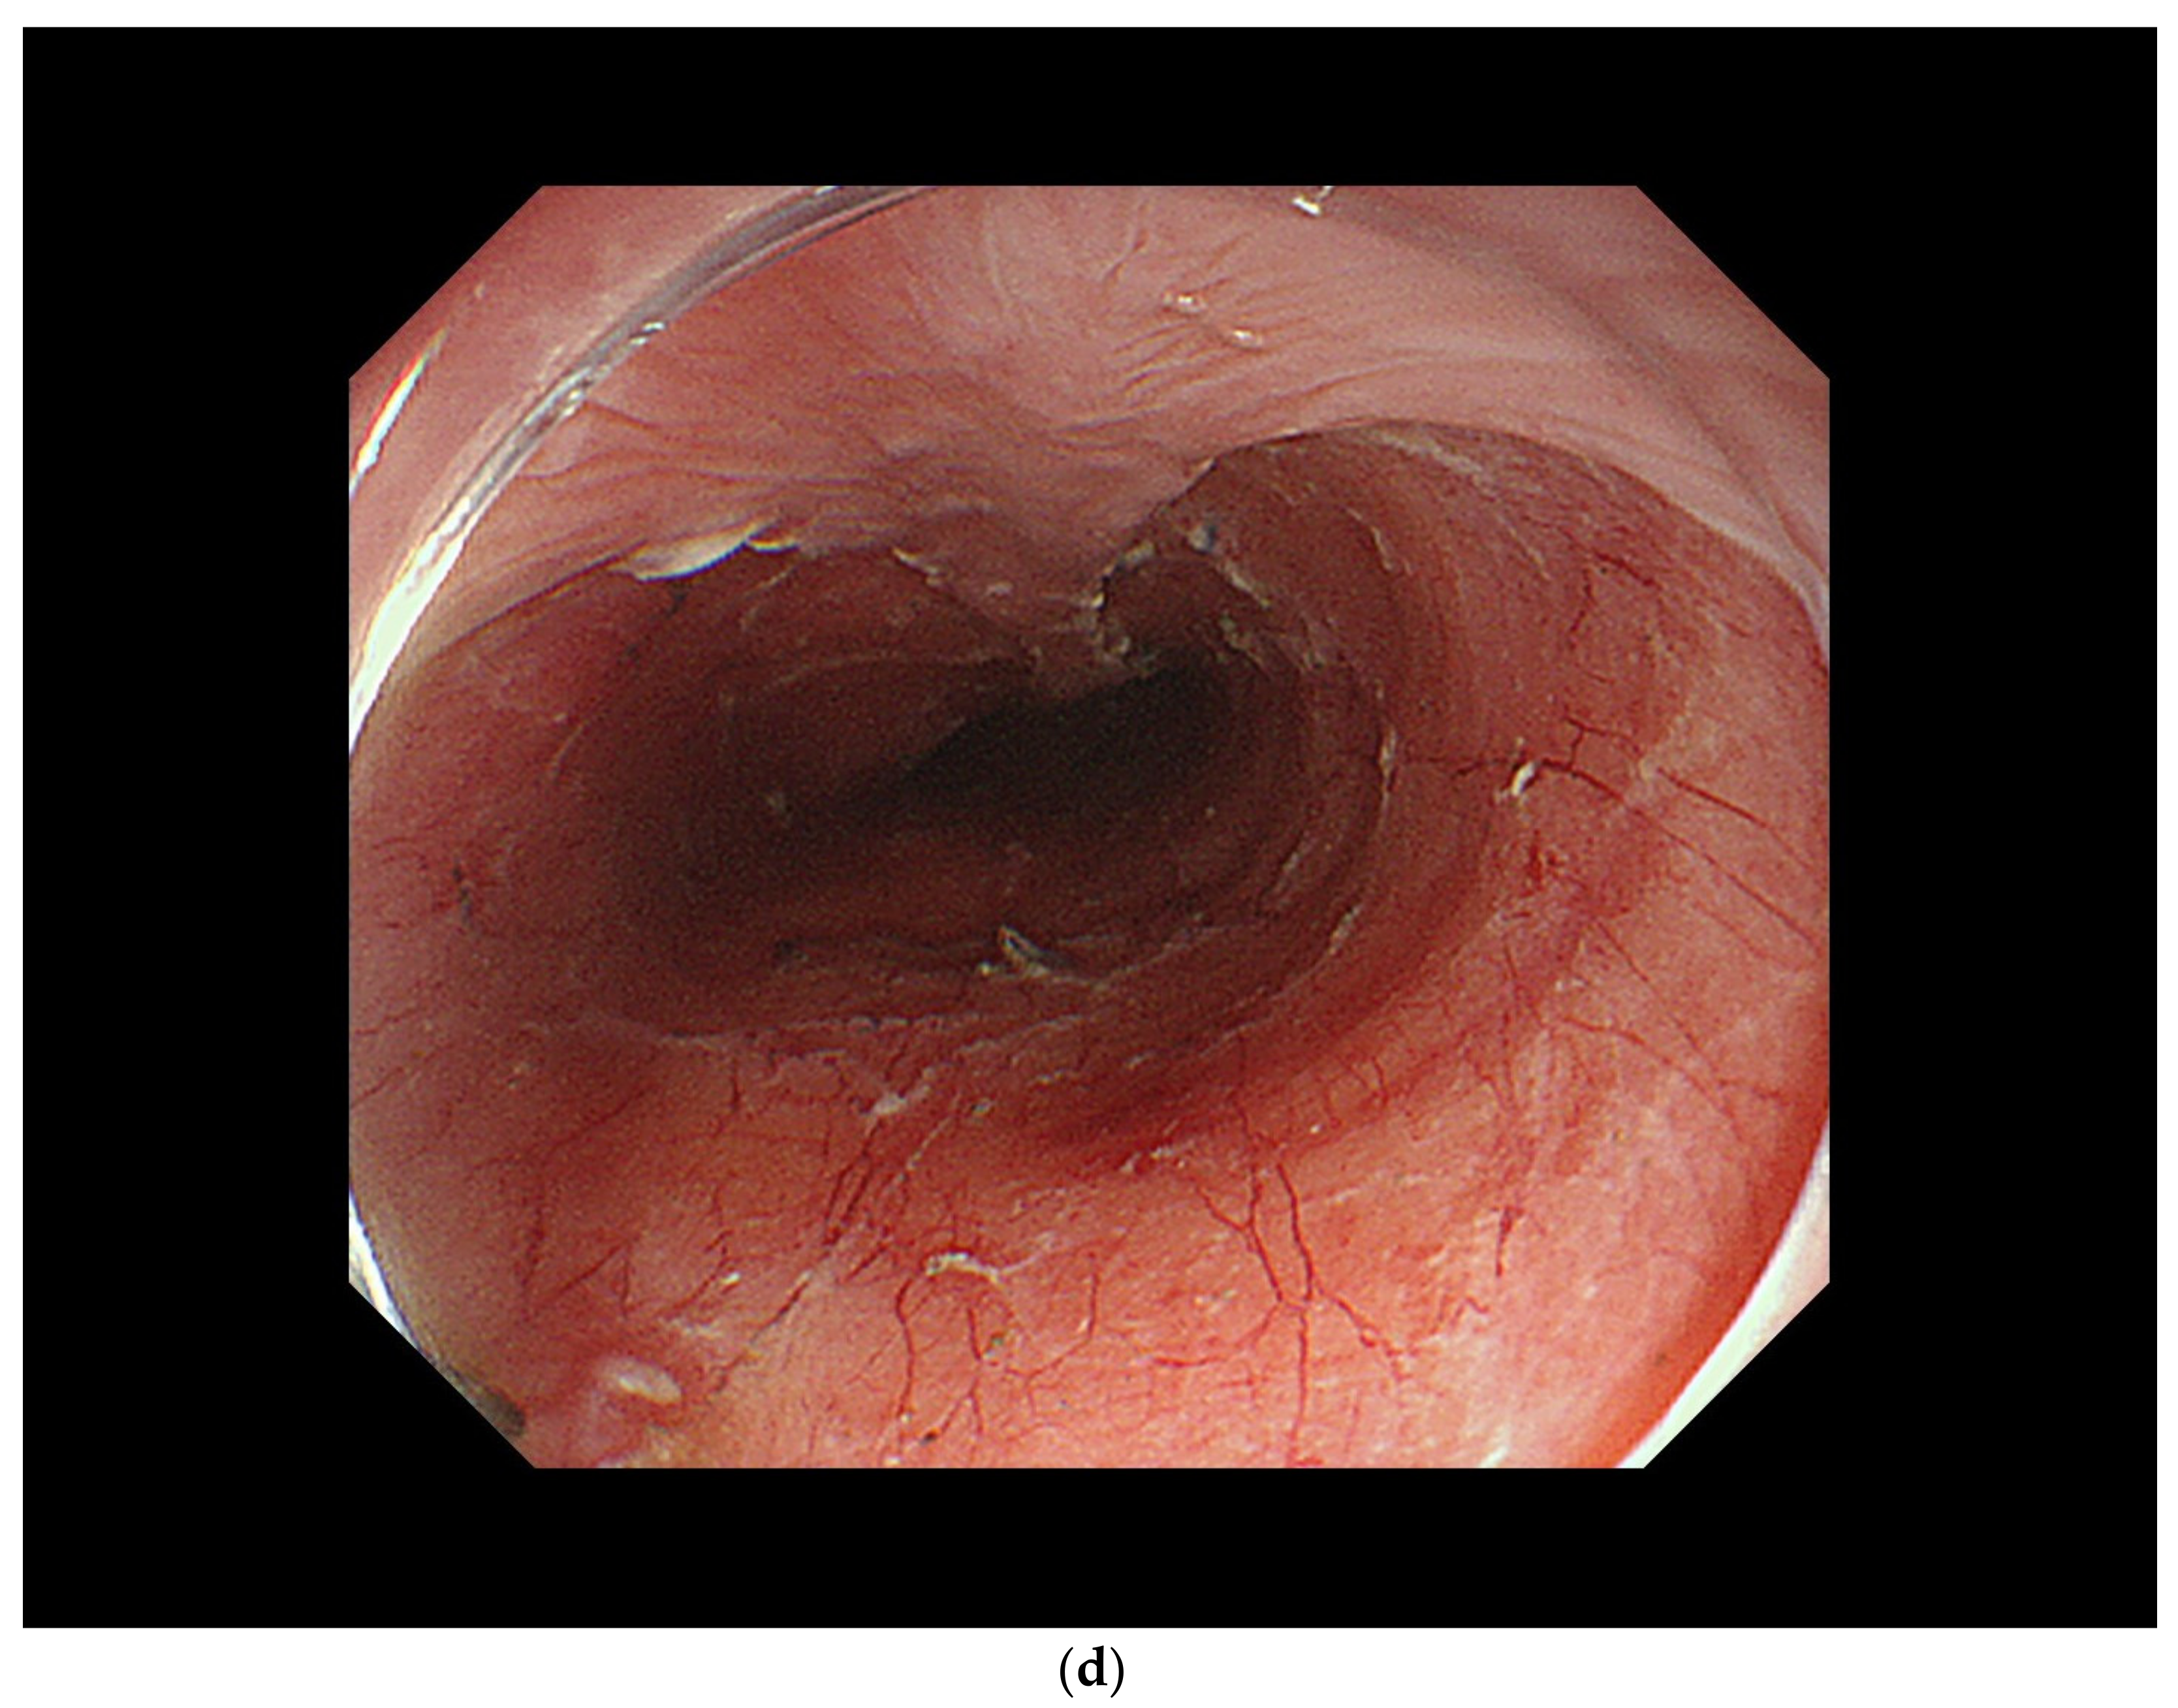

3.2. Diagnosis of Cancer Invasion Depth by White-Light Endoscopy and Magnifying Endoscopy